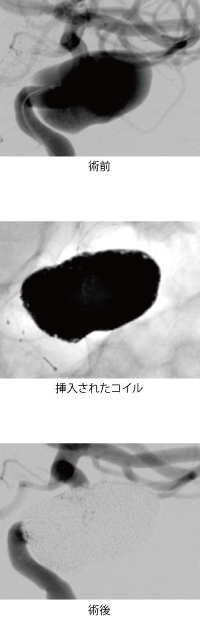

主に脳動脈瘤の破裂により発症する「くも膜下出血」では、最初の出血で約半分の方が死亡し、再出血や脳血管攣縮によりさらに残りの半分の方が亡くなります。救命できても後遺症を残すことが多く、完全に治癒する確率は2割程度とされています。

ただし、当初重篤であっても積極的な治療により完全に復帰することもあり、効果的な外科治療選択が重要です。種々の臨床研究で示された結果に基づき、当科では破裂脳動脈瘤の再出血予防の外科治療の第一選択として脳血管内手術を行っています。症例によっては従来の治療が優れているため、クリッピング手術を選択することもあります。

診療体制においては、緊急対応が重要ですが、当院脳卒中センターでは院内各所の緊密な連携により迅速な診断、治療を達成しております。当院脳神経外科では医師スタッフとして日本脳神経外科学会認定専門医7名、日本脳神経血管内治療学会認定指導医1名、専門医5名を擁しております。術者はいずれにおいても一定の技術レベルに達しており、柔軟かつ最善の治療選択を行っております。

再出血予防の外科治療後は、全例で卒中ケアユニット入室による綿密な全身管理を継続します。続発する疾患として脳血管攣縮、水頭症が重要ですが、ベッドサイドでの経頭蓋エコーモニタリング、脳血管攣縮時の脳血管内治療による介入、脳室ドレナージなど幅広い対応を行っております。重篤かつ予後不良な疾患ではありますが、積極的な全般的治療により総じて良好な治療成績を達成しております。